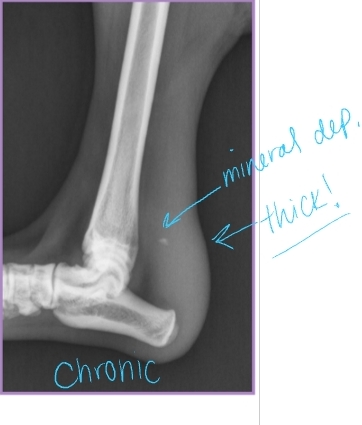

Dt: Chronic = thick tendon/minerals

Radiographs: Increased soft tissue opacity, Mineralization, Bone avulsion, Gas in soft tissue

US: Focal hypoechoic area in tendon

Tx: Surgical repair + EC (#1), (sx not option) EC w/ Hock in moderate extension 8w post-op